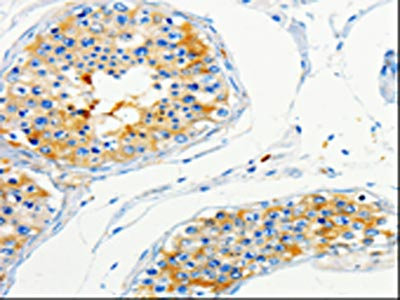

The image on the left is immunohistochemistry of paraffin-embedded Human skin tissue using CSB-PA256310(CAP1 Antibody) at dilution 1/50, on the right is treated with fusion protein. (Original magnification: ×200)